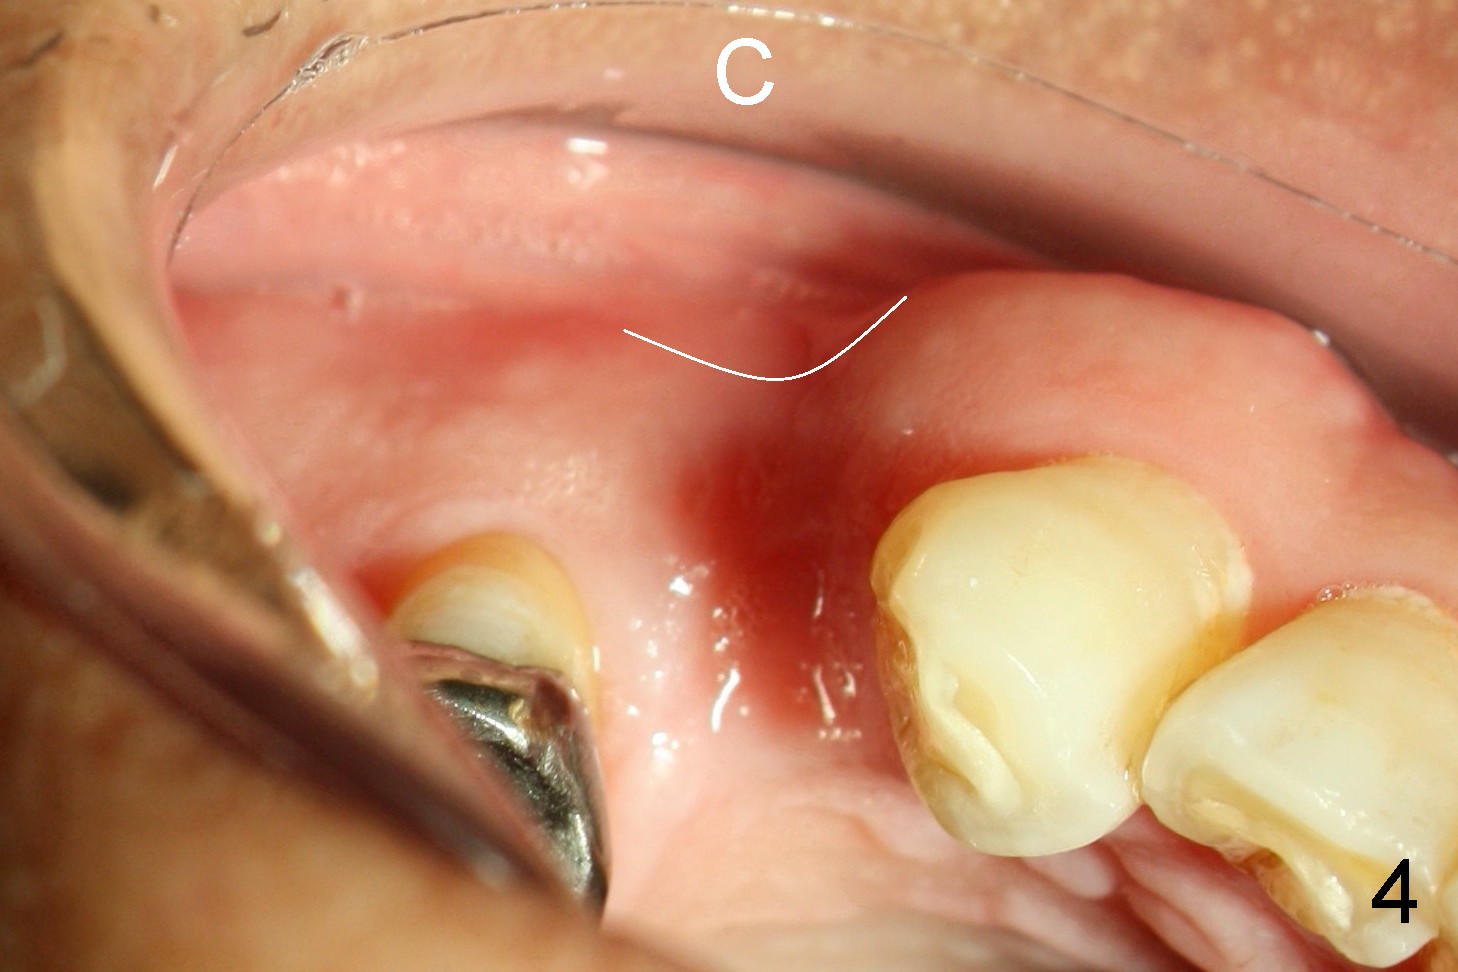

A 68-year-old man has pain and swelling associated with the tooth #5 (Fig.1). The fistula (*) is connected to the periapical radiolucency using a gutta percha (Fig.2 <). There are deep pockets distobuccal and lingual. The lingual root is found to have oblique fracture upon extraction. The distobuccal plate perforates (Fig.3). Collagen plug is placed. The buccal plate is concave (Fig.4) and socket density is low 2.5 months post extraction. Three months post extraction a 4.5x8 mm Bicon implant is placed after reamer and osteotome osteotomy (Fig.6). Bone density around the implant appears to increase 5 months post placement (Fig.7). Porcelain-fused-to-metal crown is cemented 2 weeks later. Bucco-occlusal porcelain chips 2 months post cementation. The patient decides to redo the crown. PA is taken before crown removal (Fig.8: 3 year 10 months post cementation). When a straight abutment is removed (Fig.9 A), a 15° angled abutment has to be used (Fig.10 red) for restoration.